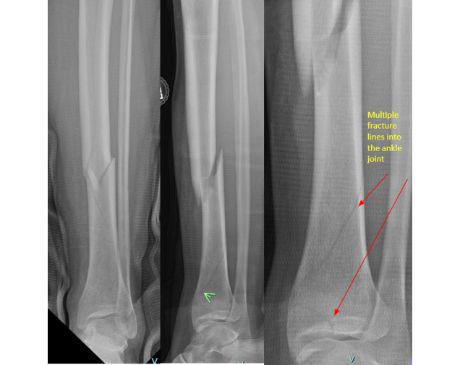

I was hit by car, had a compound fracture with a bone sticking out of my left foot. Broken tibia and fibia?. Screwed plate and bones back together. I am healing fine, next visit 3/26 to remove stiches. I seem to have total function of foot. Still have 2 more weeks of not using leg, but very hopeful.